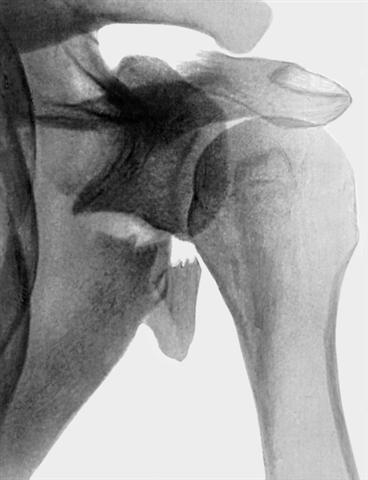

Рис. 4. Рентгенограмма области плечевого сустава (прямая проекция) при оскольчатом переломе латерального угла лопатки со смещением суставной впадины.